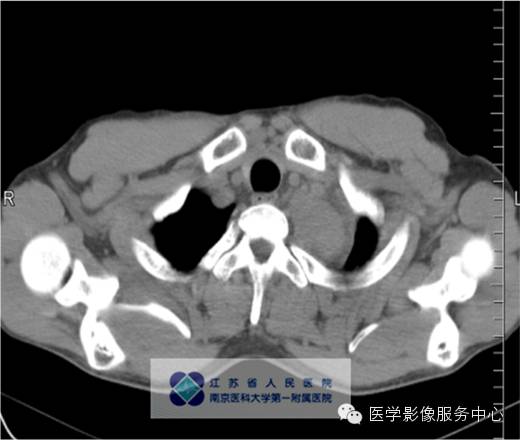

男,27岁,因“查体发现纵隔占位三月余”入院。

影像分析:左上、后纵隔内见类圆形软组织密度增高影,密度尚均匀,边缘清晰,增强扫描均匀强化。